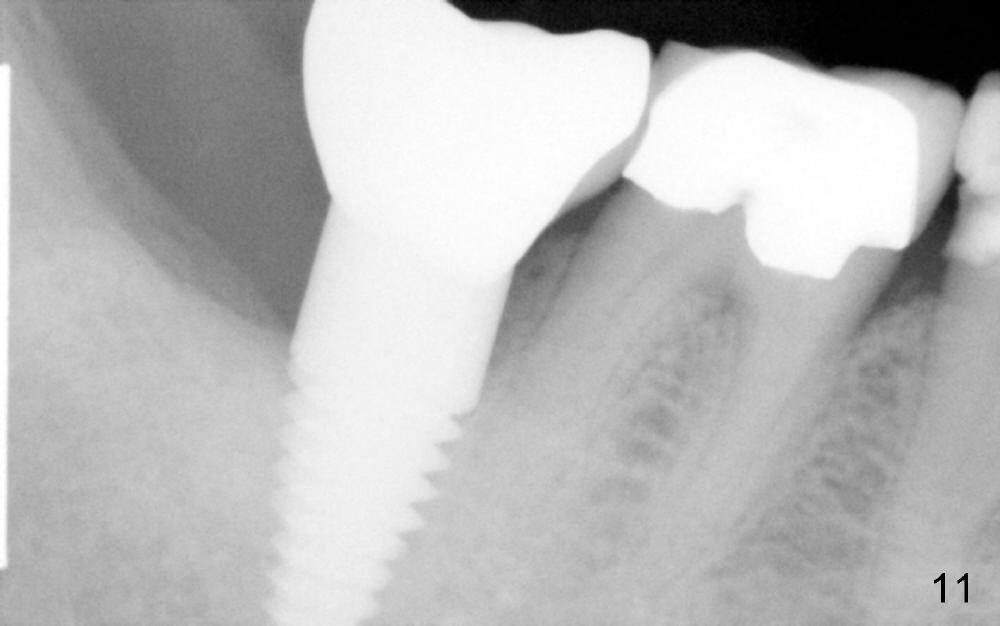

X-ray taken six months after cementation shows that there is no bone loss around the implant (Fig.11).